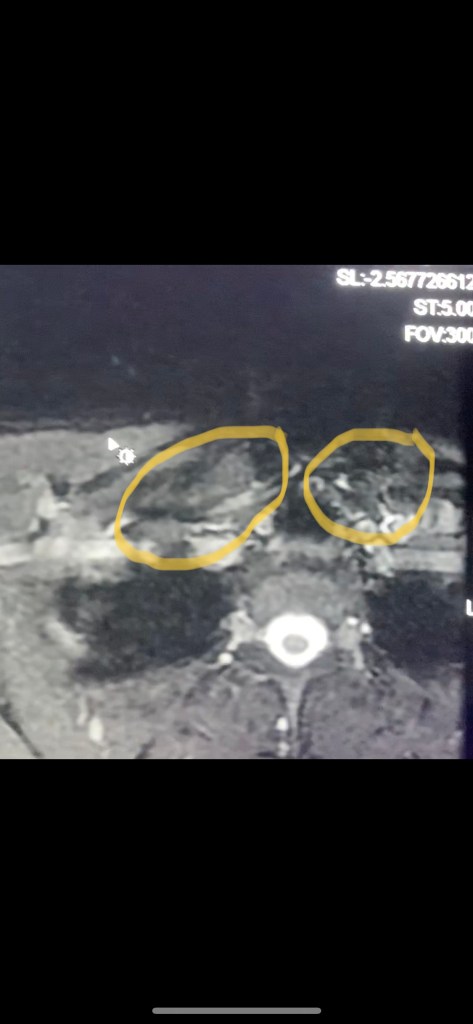

Our hospital’s vascular surgeon texted me about a mutual patient right at this time, so I thought, hey what the hell, maybe I’ll ask him if he knows anything about what I should do. I sent him the same MRI clip that I included at the beginning of this post. It was 7 seconds long. He immediately texted me back and said- your SCM muscle, clavicular head, is significantly hypertrophied (basically one of the muscles in my neck was way bigger than it should be) and that’s what’s causing the narrowing. He figured out from just a 7 second clip on his phone something I had spent months trying to do. I had shown that same clip to at least 10 other doctors at this point, in addition to the TOS “expert”, and not one person had figured that out. Once he pointed it out it was like a lightbulb finally turned on in my brain, and everything made sense. It was suddenly so obvious that I felt like an idiot.

look at the size difference between these two muscles

I had probably read at least 10 different papers on all the different potential causes of TOS at this point, and this was not listed in any of them. I did read that trauma can cause muscle hypertrophy (enlargement) but never seen this specific muscle as a cause. My best guess is that the offset alignment caused the muscle to gradually get bigger and bigger until eventually the vein hit its limit. It probably started with a small clot that dissolved on its own but caused damage to the vein which caused it to scar and narrow, and that’s when everything got suddenly worse. The clot(s) probably caused swelling which was pressing on the nerves nearby. The puzzle was finally solved, and now that I knew exactly what was causing it I could figure out how to fix it.